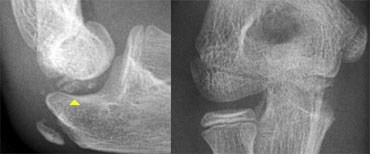

On AP-view the avulsed medial epicondyle projects over the trochlea. Lateral view shows the fragment to be trapped within the joint. On AP-view the avulsed medial epicondyle projects over the trochlea. Lateral view shows the fragment to be trapped within the joint.

Medial Epicondyle avulsion (5).

An avulsed fragment that is located within the joint can give diagnostic problems.

On an AP-view this fragment may be overlooked (figure).

When the trochlea is not yet ossified the avulsed fragment may simulate a trochlear ossification centre.